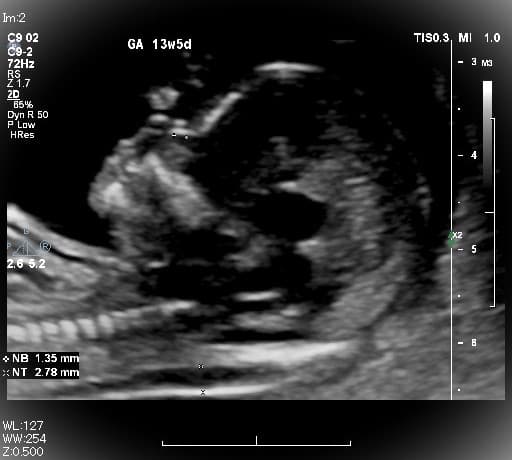

母と子のまきクリニック(Mother and fetus Maki Clinic)は、全国でも数少ない『出生前検査』の専門クリニックで【NIPT認証施設】です。妊婦健診や一般不妊治療、婦人科では小児期から、10~20代では将来を考えた『プレコンセプションケア』、更年期まで様々な女性の健康をサポートしています。 出生前検査の中でも、実施できる施設の少ない『胎児超音波精密検査(胎児ドック)』は、妊娠初期から可愛い赤ちゃんの様子や4D超音波を見て頂きながら、多くの先天性の病気のチェックができ、当日のうちに結果がでる検査です。 ・母体血による検査(NIPT・コンバインドテスト;オスカー検査)<日本医学会NIPT認証施設> ・胎児超音波精密検査(プレドック、初期・中期・後期胎児ドック)<英国FMF超音波資格> ・安全迅速な確定診断(絨毛検査・羊水検査による染色体・遺伝子検査) ご家族で初めて赤ちゃんに出会える!当院ならではの感動の出生前検査です。検査結果に合わせて赤ちゃんをしっかり診させていただき、尊い命を大切に育みながらご家族一緒にマタニティライフを楽しんで頂けるよう願っています。

出生前診断とは、妊娠中の胎児が何らかの疾患に罹患しているかどうかを検査して診断することを指します。出生前検査は赤ちゃんとご家族のための検査です。 出生前診断を行う目的は、あらかじめ出生前に胎児を診断することで、生まれてくるお子さんに病気が予測される場合には、妊娠中から適切な施設を選び、管理を行い、スムーズな治療につなげられ、適切な療育環境の提供ができます。 胎児の疾患の診断や胎児の健康状態の評価を行う出生前診断は、大きく非確定検査と確定検査に分かれます。 非確定検査とは、NIPTや母体血清マーカ―検査、超音波胎児ドックなどです。他に胎児CTや胎児MRIなどで、精密検査を行うこともあります。 確定検査とは、絨毛検査・羊水検査で染色体の数や構造を調べる検査です。この検査では、サイトメガロウイルスや風疹ウイルス、トキソプラズマなどの胎内感染を調べることもあります。 出生前診断では、実際に受ける前に遺伝医療の専門家などによる遺伝カウンセリングを受ける事が望ましいとされています。